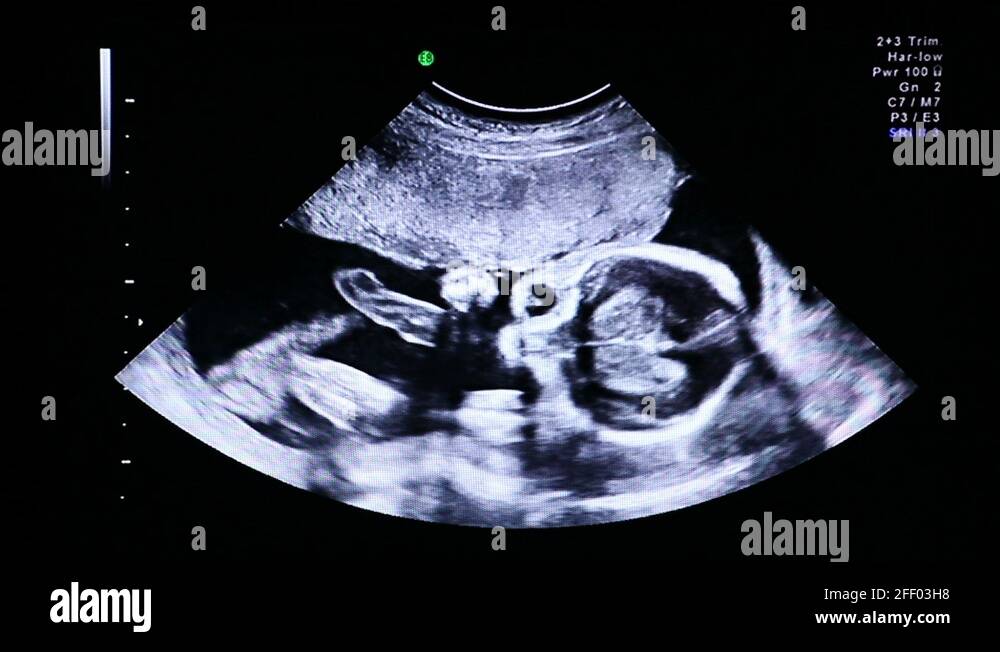

22 недели видео

3 кг за 3 недели при беременности